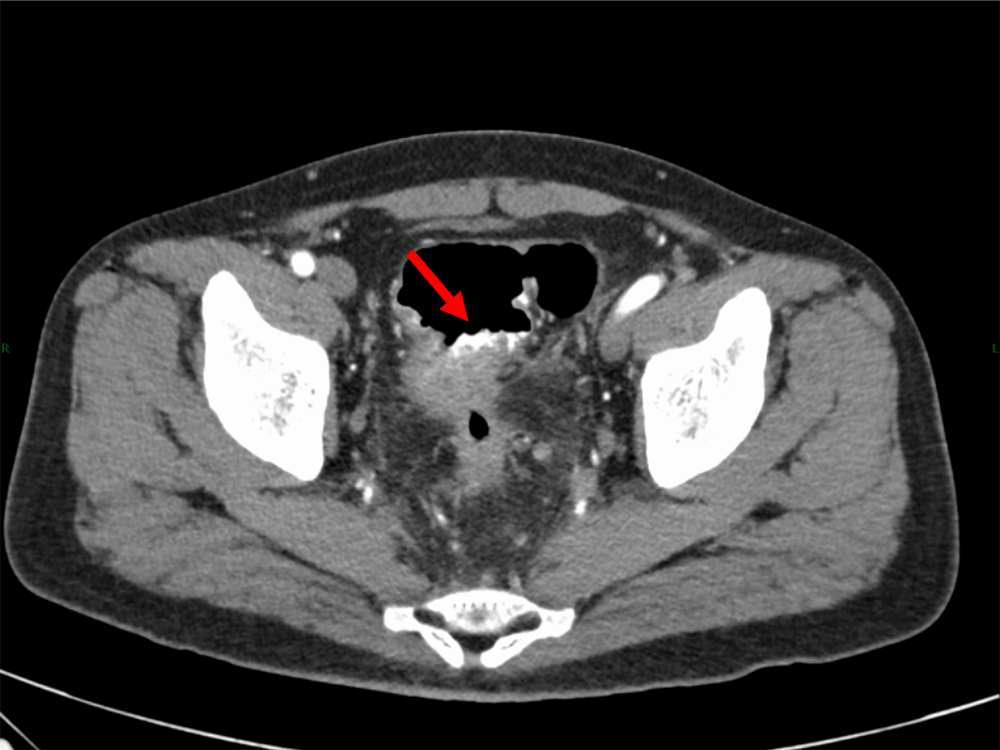

図1.単純(120kVp画像)、水平断

ガストログラフィンの貯留があり、病変の辺縁が不明瞭となっている。